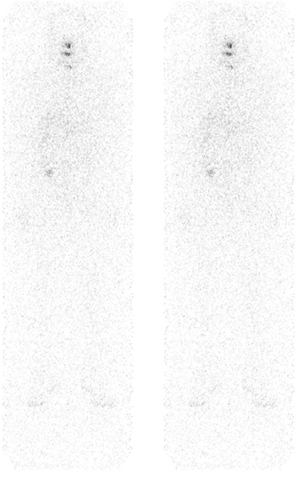

The patient was then referred to our department for radioactive iodine (RAI) therapy one month after surgery with negligible thyroglobulin level. The patient was given initially with 100 mCi capsule of radioactive iodine. Whole-body I-131 survey (Fig. 2) showed negative result after 1 year of RAI therapy. Other tests included thyroglobulin of 7.44 ng/ml (reference value: 2—70 ng/mL) and antithyroglobulin antibodies of 92.6 IU/mL (reference value: <50 IU/mL). Two months after the whole body I-131 survey, the patient palpated a small, fixed, nontender mass on the right lateral neck area. Ultrasound (image not shown) and plain CT scan of the neck (Fig. 3) were done showing a hypoechoic and enlarged lymph nodes, respectively. He was then scheduled for modified radical neck dissection (MRND) and the harvested lymph nodes were sent for biopsy. The lymph nodes of the lateral compartment (III, IV, and V, sparing II) of the neck were found to be metastatic in nature. Four weeks after the surgery, thyroid scan (Fig. 4) was done showing the absence of functioning thyroid tissue in the thyroid bed, followed by a second radioactive iodine therapy of 150 mCi thereafter. Post RAI therapy scan (Fig. 5- 6) showed residual uptake on the thyroid bed and right lower quadrant of the abdomen denoting recurrence and distant metastasis, respectively.

Figure 2: Whole body survey I-131 shows no appreciable functioning thyroid tissue in the thyroid bed with no evidence of distant metastasis.